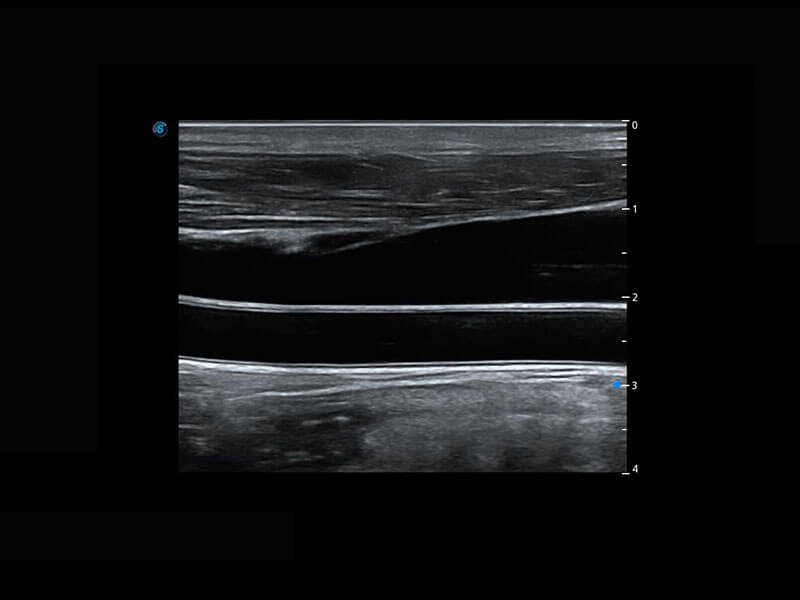

P60优异的图像质量搭载专科探头,在妇科基础疾病的诊断、卵泡生长的监测、输卵管通畅情况的判别等方面为您提供生殖应用方案。

• 腔内妇科-宫腔分离

• 腔内妇科-卵巢